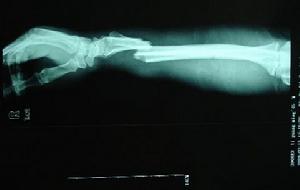

前臂外傷後疼痛活動障礙,X線片可明確骨折類型及移位情況。照片應包括肘腕關節,以了解有無鏇轉移位及上下尺橈關節脫位。

尺橈骨幹骨折本病根據其外傷病史及臨床表現可以初步確診,但還應使用一些輔助檢查的方法幫助進一步診斷,X線片可明確骨折類型及移位情況。照片應包括肘、腕關節,以了解有無鏇轉移位及上、下尺橈關節脫位。